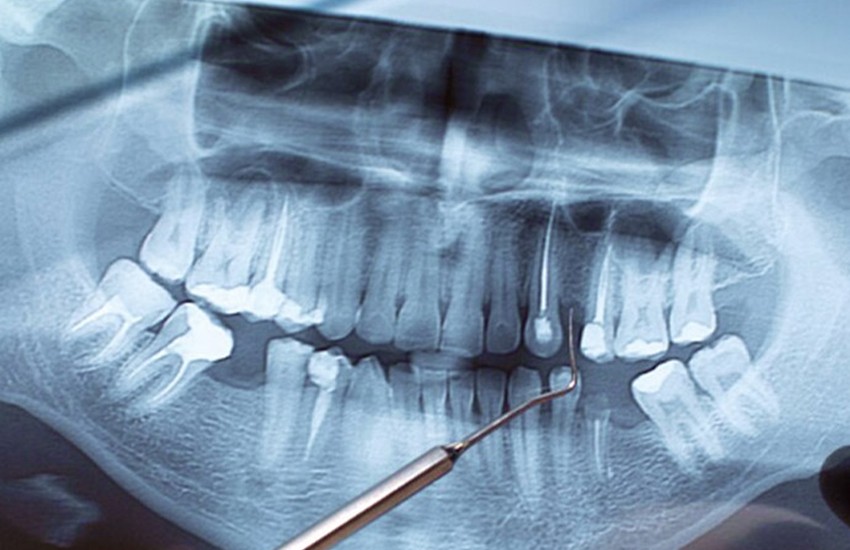

Sometimes, despite a perfectly executed root canal, an infection can linger in the microscopic branches at the very tip of a tooth's root, known as the apex. When this occurs, an apicoectomy or "root-end resection" is the most effective way to save the tooth from extraction. Rather than going back through the crown, this surgical approach allows Dr. Bulsara to access the infection directly through the gum tissue.

By removing the infected apex along with any surrounding inflamed tissue, we can effectively sterilize the area and prevent the spread of bacteria into the jawbone. This procedure is a vital line of defense for preserving your natural dental anatomy when conventional treatments are no longer an option.

At Murphy Dental Center, we perform this delicate procedure using high-powered magnification and specialized instruments to ensure total accuracy. Once the infected root tip is removed, we place a small, biocompatible filling to seal the end of the root canal, preventing any future bacterial leakage.